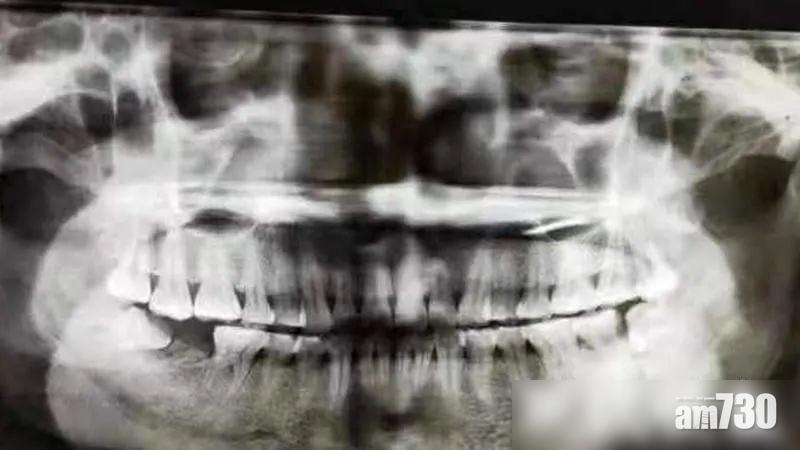

方女的牙齒狀況。(互聯網)

該院口腔科主任醫師黃錦華表示,方女平時不注意口腔衛生,出現智齒冠周炎,又無及時治療,導致齒槽骨破壞缺損,面頰被膿腫穿通,涉事智慧齒及前面第二磨牙均已壞死,兩者都要拔除。報道指,方女現已拔除壞死牙齒,預計一個月後面頰痊愈,半年後再種牙。